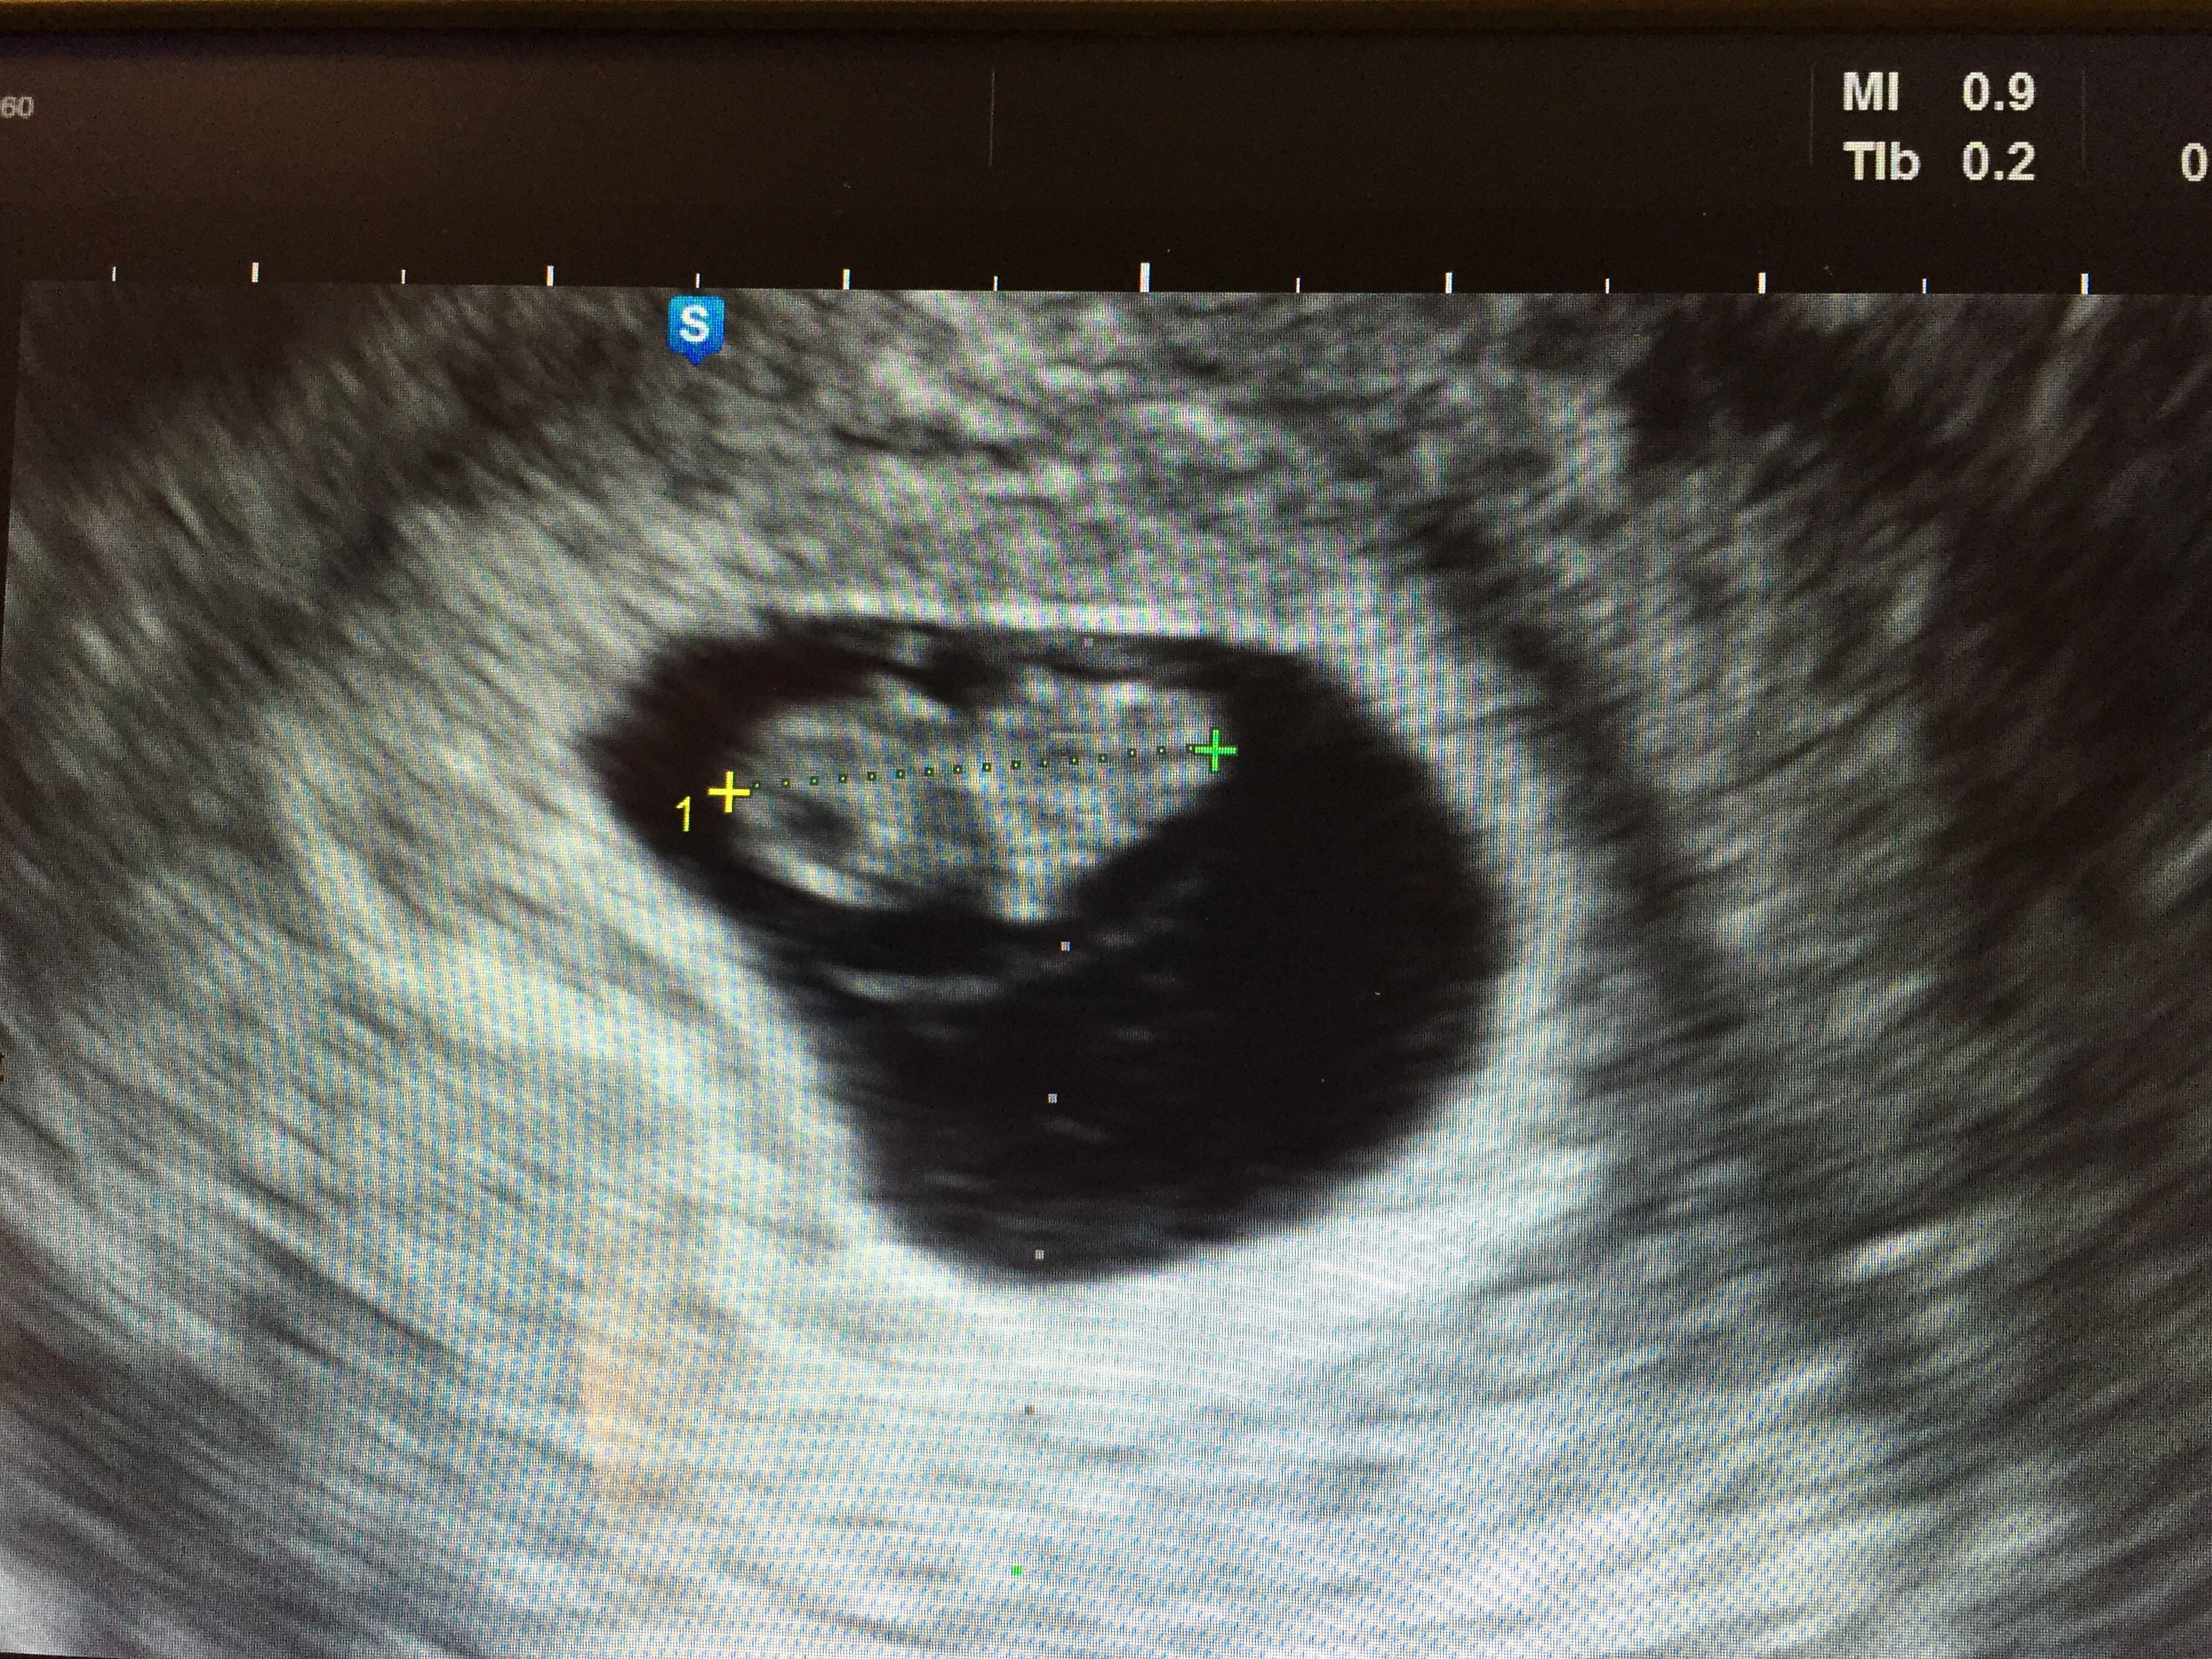

• Just got this today! We originally thought I was 11w3d, but my cycles were wacky so turns out I'm 8w4d. HR was 171bpm. <3